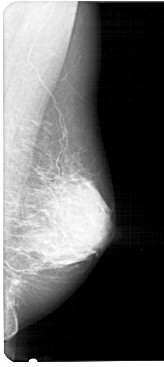

A_1280_1.RIGHT_MLO

RIGHT_CC LINES 5011 PIXELS_PER_LINE 2341 BITS_PER_PIXEL 12 RESOLUTION 43.5 NON_OVERLAY